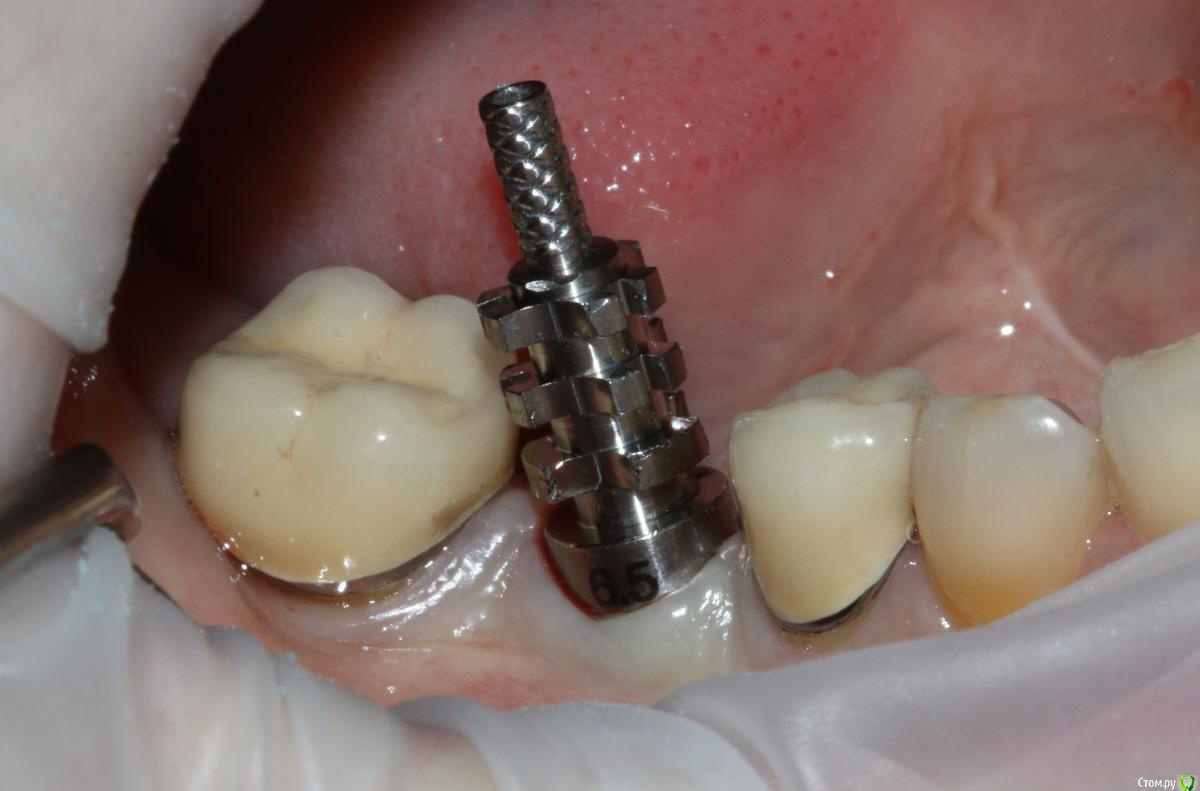

Ильдар Опубликовано 29 марта, 2015 Поделиться Опубликовано 29 марта, 2015 Коллеги, здравствуйте!Вот демонтировал старье. мк на зубы.имплант 4310, поставил поглубже.мк на имплант - техник прислал коронку с шахтой и абатмент,я склеил на fuji1. закрутил на 35 н.залепил не очень красиво , но с плавиковой, силаном и олбонд 3. думаю надежно.контрольный прицельный есть, видимо забыл его. извиняюсь за нечеткие fото. буду рад отзывам 3 Ссылка на комментарий

Фарид Расулыч Опубликовано 29 марта, 2015 Поделиться Опубликовано 29 марта, 2015 Ух как Имплант мощно заглубили) дентиум? Ссылка на комментарий

Ильдар Опубликовано 29 марта, 2015 Автор Поделиться Опубликовано 29 марта, 2015 Ух как Имплант мощно заглубили) дентиум?да, дентиум. Ссылка на комментарий

k.t.m. Опубликовано 29 марта, 2015 Поделиться Опубликовано 29 марта, 2015 все нра и прилегание коронок на зубах и витальность, но вот дентиум больше 1мм не стал бы заглублять,при отсроченном протоколе.и для одиночек снимаю закрытым методом-меньше возни 1 Ссылка на комментарий

Ильдар Опубликовано 29 марта, 2015 Автор Поделиться Опубликовано 29 марта, 2015 все нра и прилегание коронок на зубах и витальность, но вот дентиум больше 1мм не стал бы заглублять,при отсроченном протоколе.и для одиночек снимаю закрытым методом-меньше возниЗаглублен только относительно язычной кортикалки. Я не покупал трансферы для закрытой, а надо ) Ссылка на комментарий

Nemiroff Опубликовано 12 апреля, 2015 Поделиться Опубликовано 12 апреля, 2015 (изменено) в каталоге дентиум написано, что абатменты фиксируются усилием 25-30 ньютон. при большем усилии, если вы будете пытаться открутиться с конусной системы, то имеете высокий риск сломать винт, сорвать шахту винта или просто не открутить ничего. показаний к заглублению в данном клиническом случае нет на мой взгляд.а показания к круговой гирлянде не соседних зубах заключались в их витальности и необходимости сделать тонкий переход края коронки в тонкий уступ? Изменено 12 апреля, 2015 пользователем Nemiroff Ссылка на комментарий